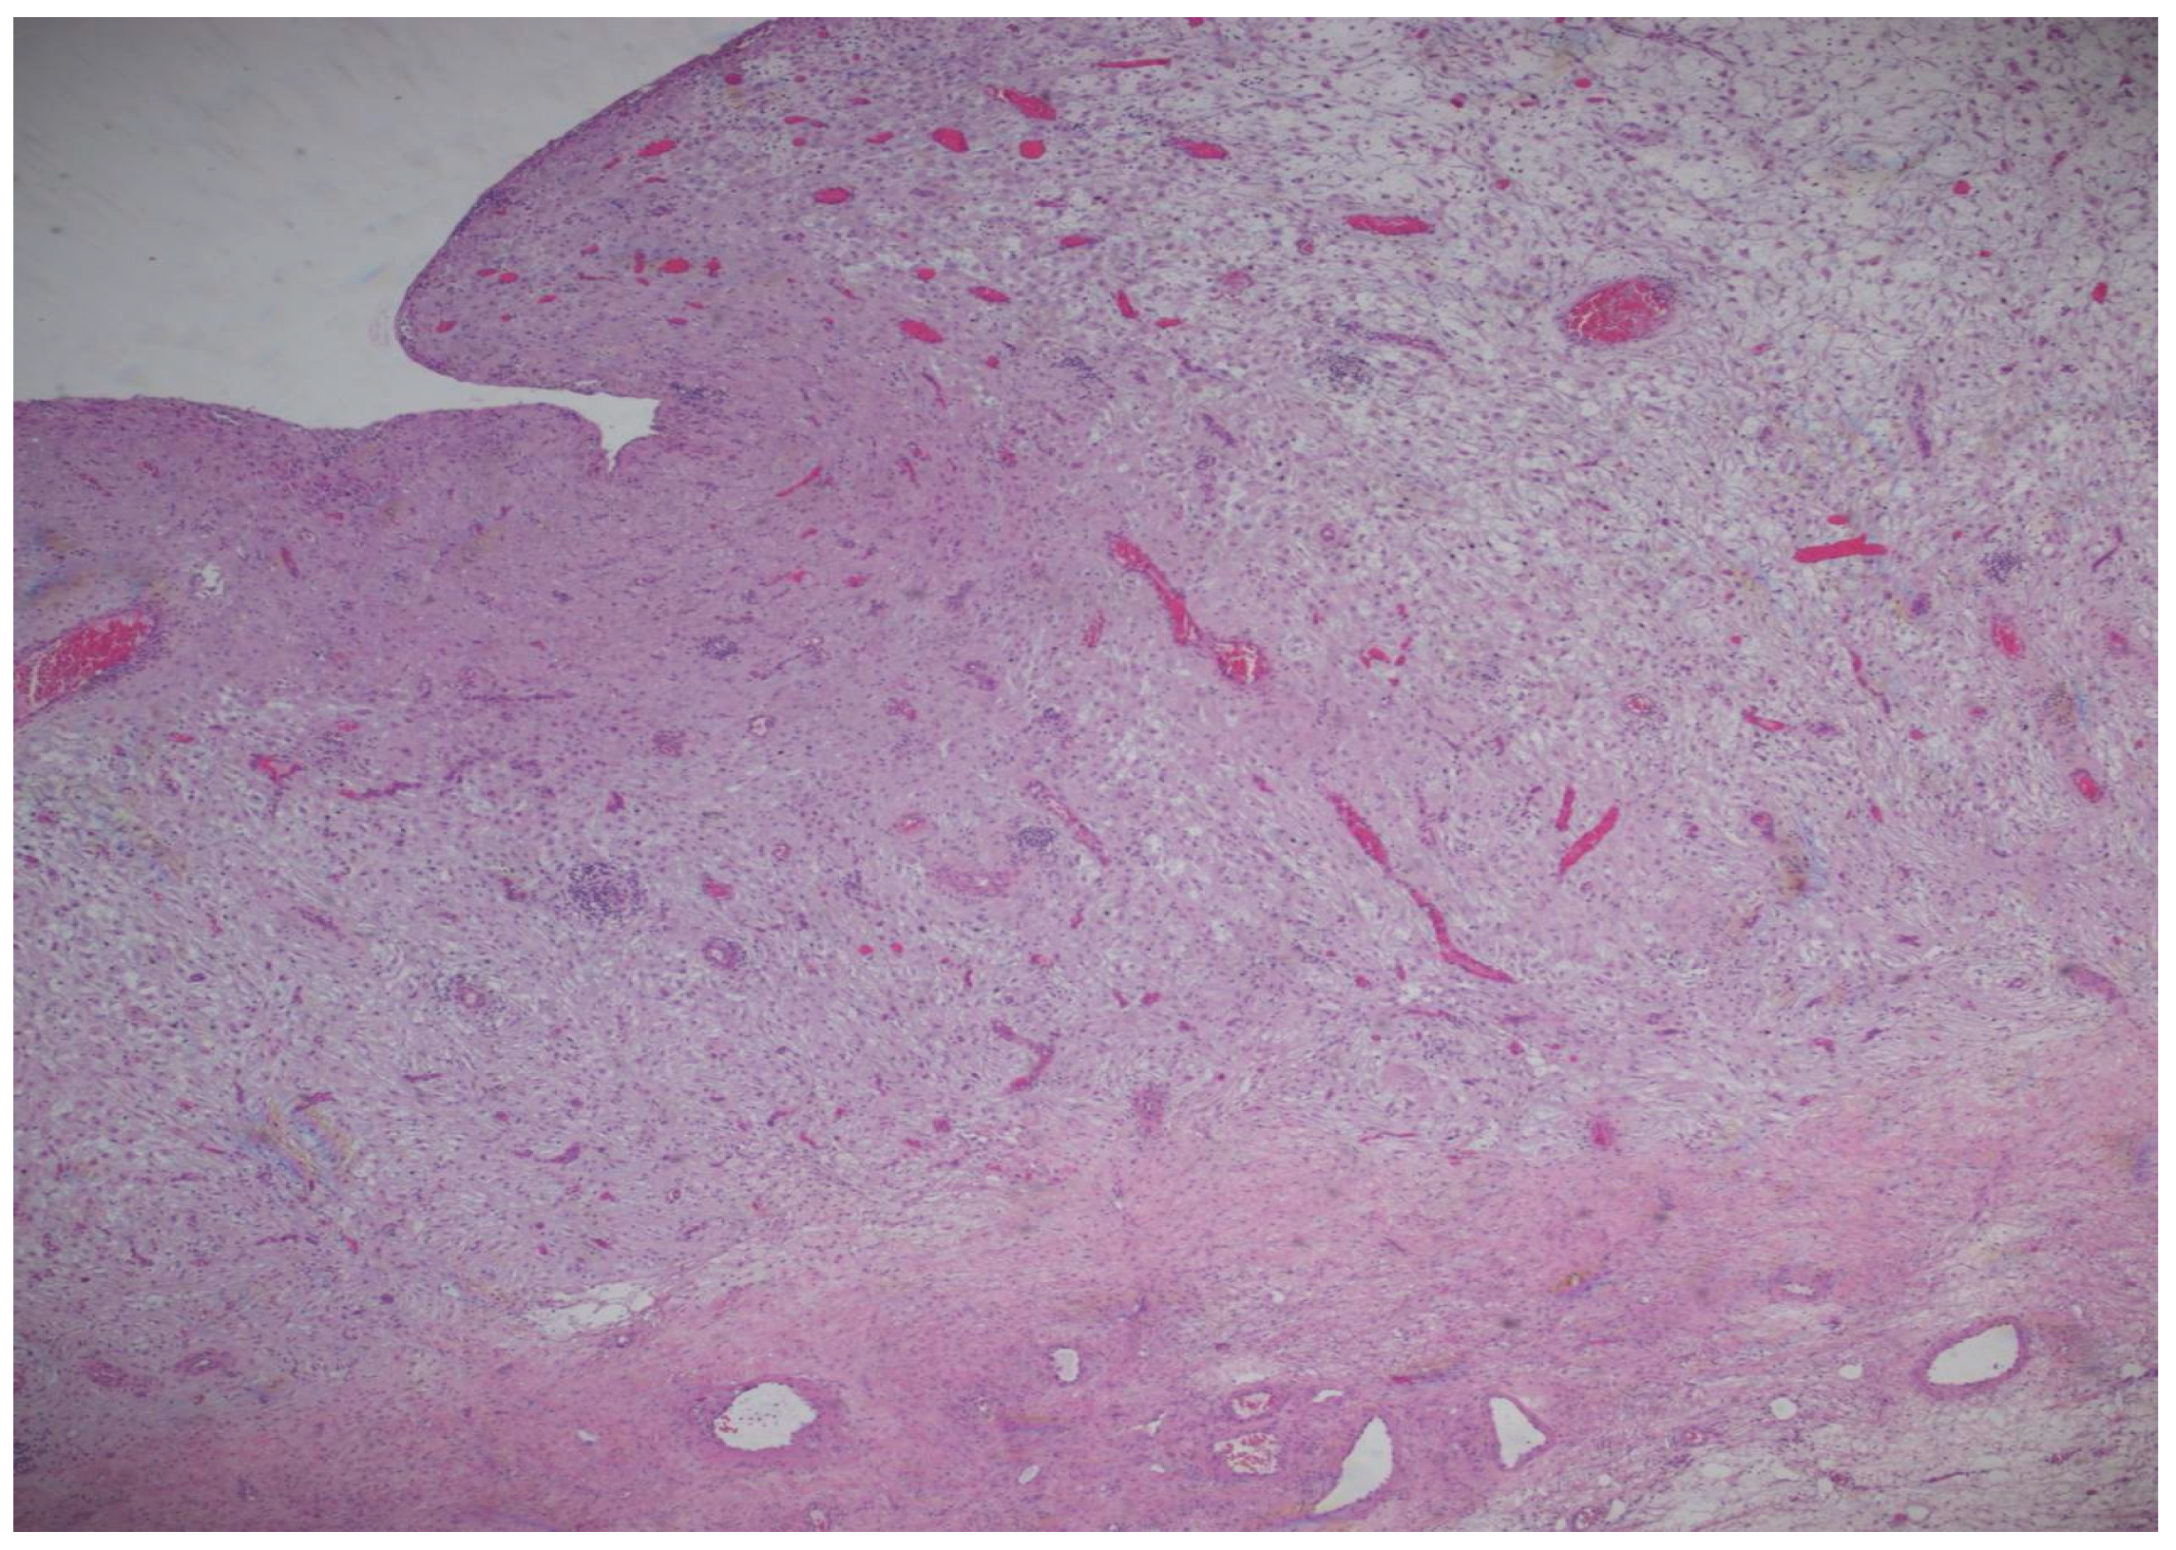

The histopathological result came as follows: (1) Polypoid ovarian endometriosis, pregnancy-induced changes. (2) Right ovarian serous cystadenoma. ICD-O: 8441/0. 3. Peritoneal fluid and benign cytology (Figure 8 and Figure 9).

The microscopic examination reveals a decidualized stroma exhibiting rare capillary formations, small lymphocytes, and small clusters of hemosiderin-laden macrophages (serving as an indirect indicator of endometriosis). Notably, there is an absence of endometrial-type glands within the stromal tissue.

Figure 8. Microscopic image stained by hematoxylin–eosin at 100× magnification. The cyst exhibits a polypoid architecture, characterized by polygonal cells with a decidual appearance, and a delicate capillary network diffusely distributed.

Figure 9. Microscopic image stained by hematoxylin–eosin, at magnification 200×.